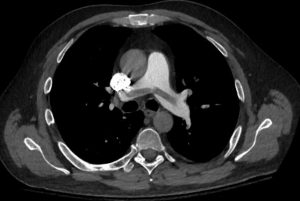

A saddle PE is a pulmonary embolism that is located over the main pulmonary arteries. Perhaps surprisingly, many patients do not have symptoms. In fact, many had imaging for another reason and the PE was an incidental finding. However, sometimes these central clots block cardiac outflow enough to cause syncope, acute right heart failure and even death.

In medical practice finding a saddle PE sometimes results in concern. The name itself seems to invoke respect by many clinicians. Of course, any proximal pulmonary embolism is a reason for concern. But it actually turns out that the location of the clot has little relationship with patient outcomes. In fact, many patients with saddle PE are asymptomatic. Having said that, this is not always the case. Sometimes the PE causes acute right ventricle failure. This can result in acute syncope and even in death.